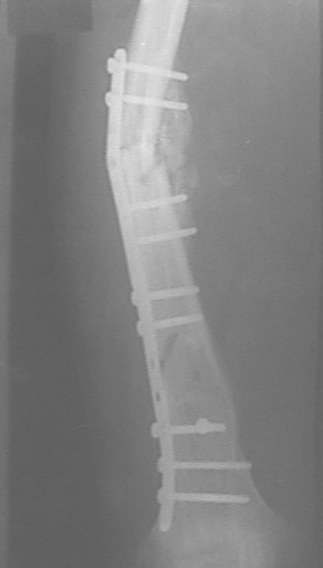

У нас, наверно, была бы сделана чрескожная остеотомия малоберцовой кости, формирование и рассверливание канала большеберцовой, закрытая остеоклазия, и закрытое же штифтование. За счет устранения варуса дефицит длины уменьшится. Можно и подтянуть дистрактором одномоментно.

При невозможности или чрезмерной травматичности одномоментного восстановления длины можно пойти двухэтапно (аппарат, потом гвоздь). Похожий пример см. тут. Прошло уже года полтора после остеосинтеза. Может, коллега Зырянов покажет годичный результат, если есть?

Александр Николаевич, к сожалению больной не является на контрольные осмотры. Я последний раз видел больного, когда прошло 7 месяцев после операции БОС. У него все хорошо. Каких либо жалоб и ограничений в нагрузке нет. Высылаю снимки до операции и последние снимки.